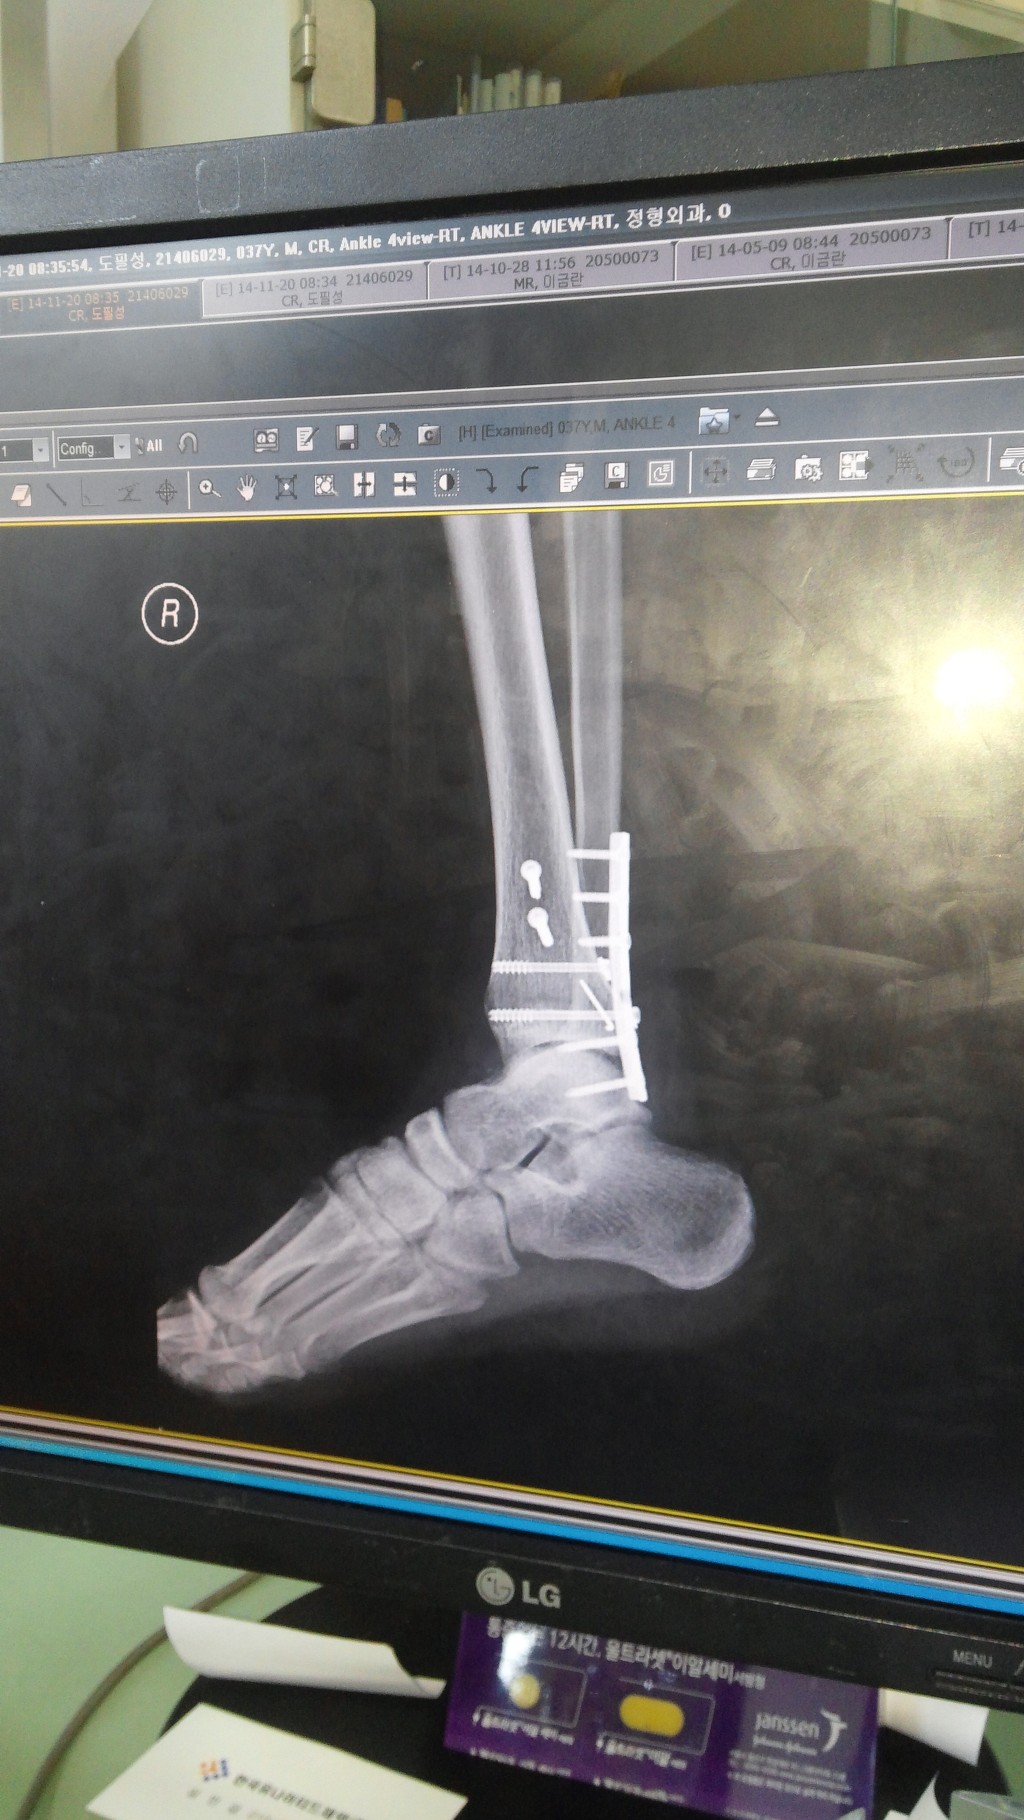

우측 족관절 원위 경골 관절내 골절, 외측과 골절, 후과 골절 수술 및 재활 과정 적습니다.15주차입니다.

다행히 붓기가 빠져서 13일 수술하였습니다. 4시간 수술하였고요. 하반신 마취하였습니다. 무통 달아놔서 그런지 큰 통증은 없었습니다.수술후 마취가 안 풀려 오줌은 마려운데 나오지가 않으니 통증이 장난 아니더군요. 휴~

8월 13일 수술

11월 25일 수술한 병원 진료. 사진 찍고 잘 붙었다며 이제 핀 제거 할때 오라고 하시네요. 수술후 1년에서 1년 6개월 후에 빼라고 합니다. 검색해보니 제거하니 엄청 부드럽고 편하다고 하네요. 저두 최대한 빨리 빼고 싶네요. 얼른 내년 여름이 와서 제거하고 싶네요.